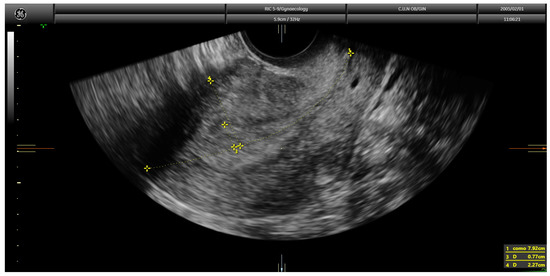

Finally, in the Karlsson’s approach, the ratio between the maximum anteroposterior diameter of the endometrial lesion and the uterine anteroposterior diameter, both measured in the sagittal plane, is estimated. Similar to the Gordon’s approach, if the ratio is <50%, myometrial invasion is estimated as less than half of the myometrium; in contrast, if the ratio is >50%, it is classified as more than half of the myometrium (Figure 2).

Figure 2. Transvaginal ultrasound showing a case of superficial infiltration in endometrial cancer using the Karlsson’s method. The ratio endometrial thickness/uterine anteroposterior diameter was 25.3%.